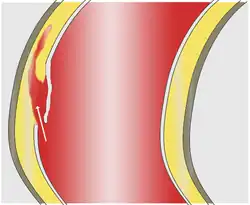

Quando a área deformada do vaso toma forma esférica, dá-se o nome de aneurisma saciforme ou sacular (de saco), ou quando tem forma alongada através do eixo principal do vaso, aneurisma fusiforme (de fuso).

O aneurisma sacular se desenvolve na parede de artérias com defeitos congênitos decorrente do aumento do fluxo sanguíneo ou pressão arterial, entre outras causas. É comum esses aneurismas se romperem, provocando hemorragia cerebral, causando até um acidente vascular encefálico hemorrágico (mais conhecido como derrame cerebral). É bastante perigoso e acarreta hemorragia com frequência.